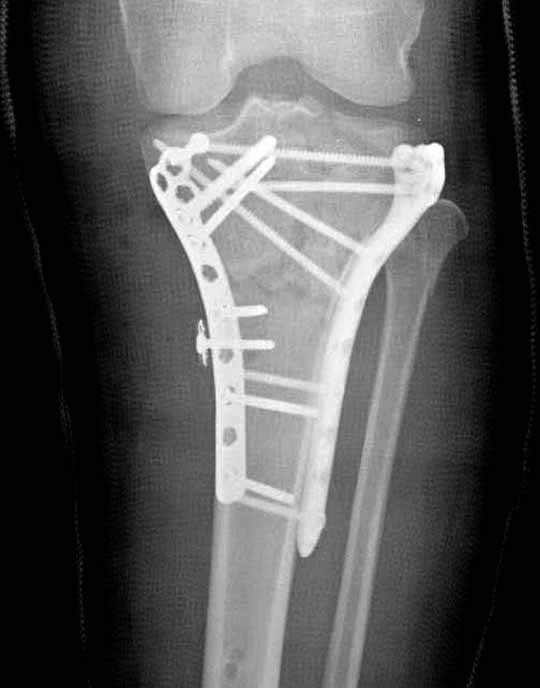

В приложении этапы фиксации Both Column Fx и пластиной Synthes для плеча при переломе медиального мыщелка.

Для изолированных переломов медиального тибиал плато, фиксацию можно провести “медиальной пластиной”. Некоторые компании, например Smith & Nephew делают медиальные и медиально-задние пластины, но они мягкие, и легко можно создать нужный контур. Жесткость создается за счет фиксации жесткими пластинами, например экстра артикулярной пластиной для дистального плеча от Synthes. Медиальный доступ тоже не из легких, надо работать между pes and medial gastroc.

Частая ошибка, когда фиксацию двух колонного перелома проводят одиночной пластиной, т.е с одной стороны, и такая фиксация не удерживает, происходит вторичноое смещение. Необходимо нейтрализовать второй пластиной или дополнительным наружным фиксатором.

Если у вас, кроме пластины, нет другого альтернативного варианта, тогда, учитывая мягкотканые проблемы с наружной стороны, я бы рекомендовал операцию делать в два этапа. Преимущества, сперва репозиция и фиксация перелома с медиальной стороны, а затем, после улучшения состояния мягких тканей, зафиксировать с латеральной стороны. Современные пластины имеют латеральный Jig для перкутанных мини доступов.